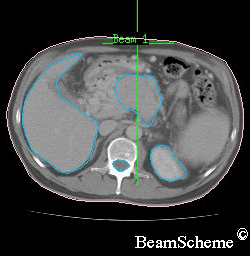

This picture shows how 3 radiation beams can be directed at the cancer. The white lines show the middle of the beams. The beams are actually like torch beams so they get wider as they travel away from the radiotherapy machine. By the time they reach the cancer each beam may be up to 8 to 10 cm in width.

This picture is of the bottom of the rib cage.

on the left is a large crescent – this is the liver

on the right, at the bottom, is a round shape – this is the kidney

in the centre, at the bottom, is a smaller round shape – this is the spinal cord inside the backbone

in the middle is an irregular shape – this is the pancreas with a cancer inside it

One beam is aimed from in front of the patient. This is the beam at the top of the picture.

The other two beams are aimed from the sides at an angle so that they avoid the spinal cord and kidney.